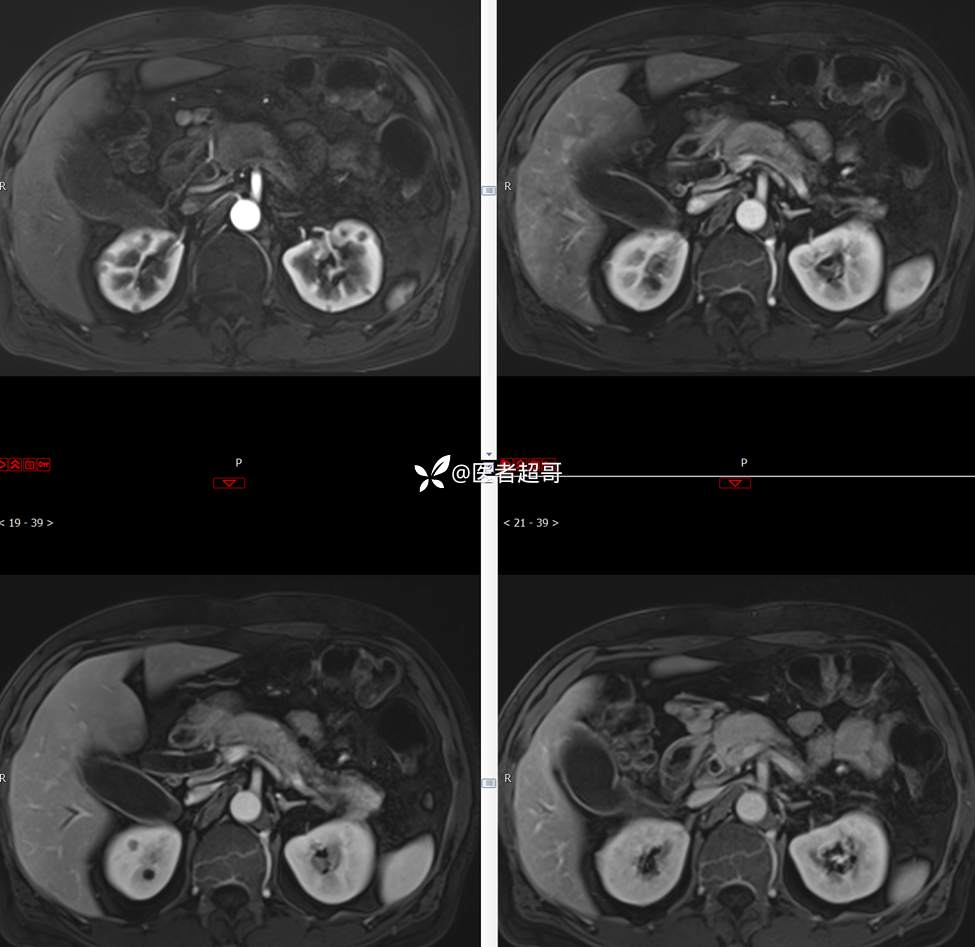

【影诊笔记772】腹痛就诊,发现肾脏病变,CT、MRI齐全,请高诊!

男,63岁 0200825 01

主 诉:间断腹痛15天

现病史:患者15天前无明显原因及诱因出现腹部疼痛不适,呈间断性钝痛,右下腹为著,无尿频、尿急、尿不尽,无发热、寒战,无腹胀。于市中心卫生院住院治疗,超声示:胰头低回声包块,胆系扩张,左肾囊肿,胆囊壁毛糙,胆囊内胆汁淤积。患者为求进一步诊治,遂以“肾盂肿瘤”收入院,患者自发病以来,神志清,精神可,饮食睡眠可,大便无明显异常,近期体重无明显增减。

既往史:既往体健